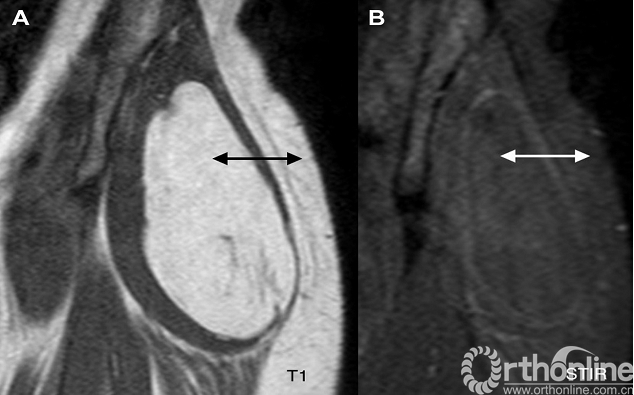

影像学特点:在超声中显示为均匀的低回声肿块。CT上为均匀的低密度影像。MRI主要表现为肿块与附近皮下脂肪有相似的信号(图1)。其中有个特例—皮下脂肪瘤,即使肉眼可见有明显的肿块,但在MRI上区别不明显,主要是因为脂肪瘤的脂肪信号与周围的皮下脂肪混合在一起。这种情况下可将肉眼可见的、可触及的皮下肿块和在MRI上无明显肿块相结合来加以诊断。

图1. 肌肉内脂肪瘤,臀部MRI的T1加权像(A)和脂肪抑制序列(STIR)(B)均显示肿瘤组织与附近皮下脂肪相同信号表现(双头箭头)。